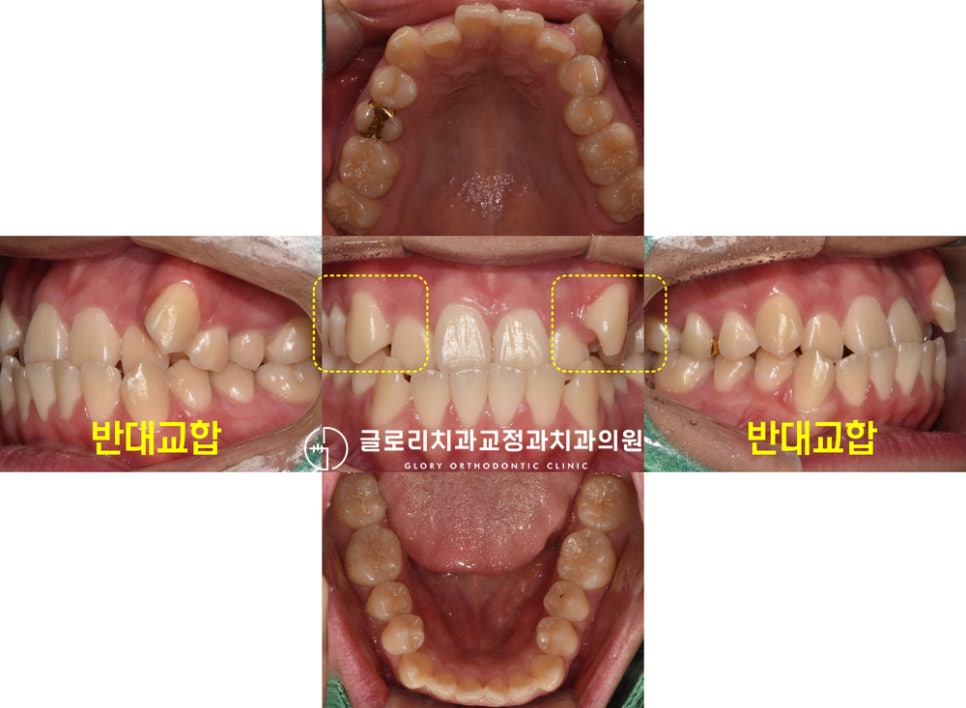

“이가 거꾸로 물려요.”

덧니와 거꾸로 물리는 반대교합으로

망우역 치과 에 오셨던 분입니다.

거꾸로 물리는 치열과 덧니로 인해

고민을 갖고 계셨던 분인데요.

실제 구내 사진을 보면 부정교합의 정도가

꽤나 심하게 나타나 있는 것을 볼 수 있었습니다.

이런 경우 저작기능도 제대로 할 수 없기 때문에

식사도 편하게 하지 못합니다.

라면과 같은 면 종류의 음식은

끊어 먹지 못할 정도로 불편함이 크죠.